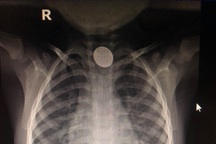

Lúc 14h ngày 8/3, bé V. vô tình nuốt phải pin cúc áo. Gia đình nhanh chóng đưa bé đến bệnh viện gần nhà, chụp X-quang phát hiện dị vật pin mắc ở thực quản ngang mức xương đòn.

Vị trí pin cúc áo trong cổ bệnh nhi (Ảnh: Bệnh viện cung cấp).